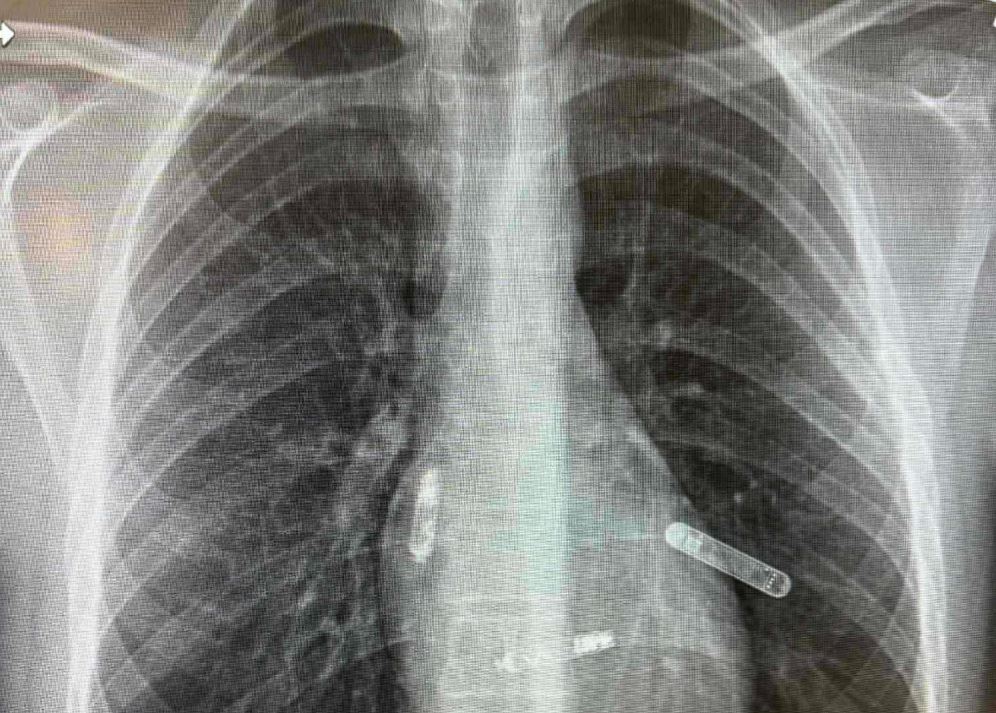

Kako je na društvenim mrežama objavio dr. Edhem Čustović, Mostarka, dr. Svjetlana Tišma-Dupanović, kardiologinja i pedijatrica, uspješno je pacijentu ugradila dvokomorni pejsmejker direktno u srčane šupljine — u pretkomoru i komoru — koji sinhronizovano stimulišu pravilan rad srca.

"Ovo je prva takva operacija izvedena na Floridi, a ujedno predstavlja veliki napredak u liječenju bolesti srca, posebno za pacijente sa poremećajima srčanog ritma i slabijom pumpnom funkcijom srca. Tradicionalni pejsmejkeri postavljaju se ispod kože grudnog koša, a žice prolaze kroz vene do srca. Nova tehnologija, koju je primijenila dr. Tišma-Dupanović, omogućava direktnu ugradnju uređaja unutar srca — bez žica koje prolaze kroz krvne sudove. Ovaj dvokomorni (biventričularni) pejsmejker sinhronizuje rad pretkomora i komora, čime se postiže pravilniji ritam i veća efikasnost pumpanja krvi", napisao je Čustović.